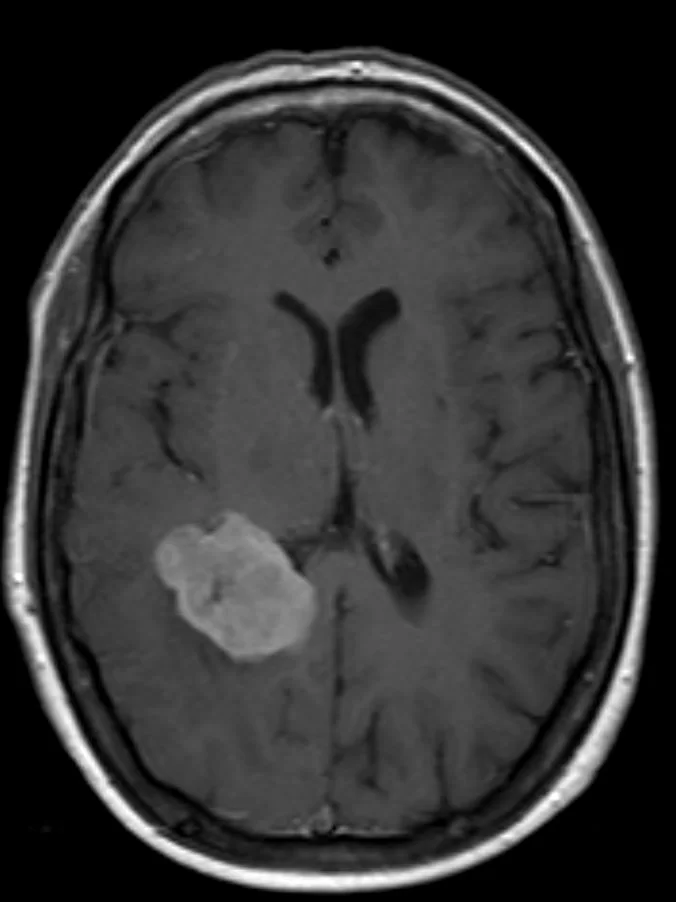

Η μαγνητική τομογραφία ανέδειξε ευμεγέθη χωροκατακτητική εξεργασία εντός της δεξιάς πλάγιας κοιλίας του εγκεφάλου.

Εδώ είναι η θέση του μηνιγγιωματος που αποτελεί τη χειρουργική πρόκληση. Πρέπει κανείς να φθάσει στον όγκο προκαλώντας την ελάχιστη βλάβη στον υπερκείμενο υγιή εγκέφαλο.